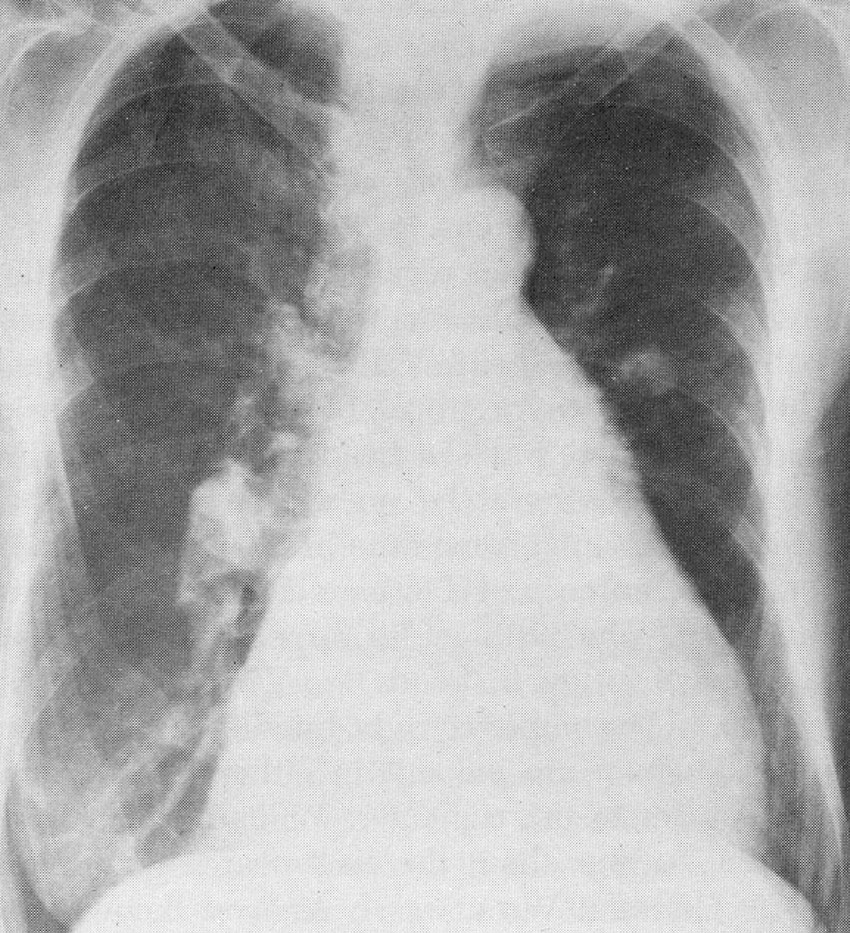

You are asked to read the chest x-ray and interpret the heart sounds of an

eighty-six year old woman who is complaining of dyspnea and who appears mildly cyanotic

on physical examination. The heart sounds were recorded over the left second intercostal

space.

The chest x-ray reveals evidence of right atrial and right ventricular enlargement and severe chronic pulmonary hypertension (enlarged main pulmonary artery segment). In the video, one can hear and see the fixed split of the second heart sound, a finding diagnostic of an atrial septal defect; also noted is a systolic flow murmur.